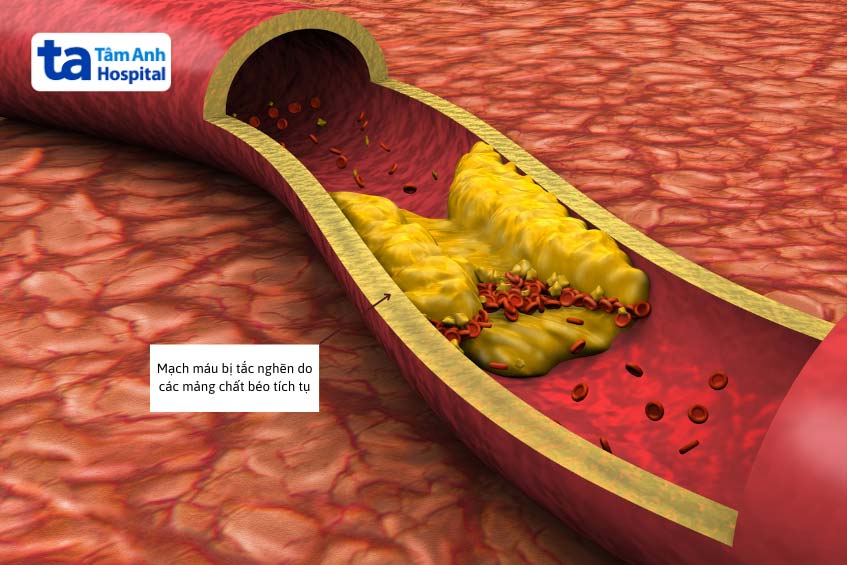

Stent được sử dụng trong điều trị bệnh lý mạch vành, tình trạng xảy ra khi các mảng xơ vữa tích tụ khiến lòng mạch bị hẹp lại và làm giảm lưu lượng máu đến cơ tim. Khi máu không đủ nuôi tim, người bệnh có thể gặp phải các triệu chứng như đau thắt ngực, khó thở, thậm chí là nhồi máu cơ tim.

Stent kim loại trần là khung kim loại đơn thuần dùng để giữ lòng mạch luôn mở. Tuy nhiên, sau khi đặt mô sợi có thể phát triển quá mức quanh stent, dẫn đến tái hẹp trong stent và cần can thiệp lại. Trong khi đó, stent phủ thuốc được phủ một lớp thuốc ức chế tăng sinh tế bào, giúp giảm nguy cơ tái hẹp đáng kể so với stent kim loại trần. Đây là bước tiến trong điều trị bệnh mạch vành, đặc biệt hiệu quả với các tổn thương phức tạp.